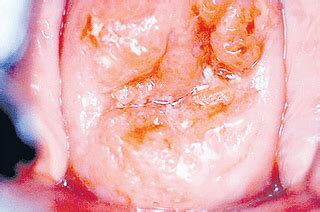

Tanda kanser rahim?posted on 21 november 2012 by zainura66 barah pangkal rahimpendarahan selepas persetubuhan.berlakunya pendarahan selepas. Alamak, kenapa ada pendarahan selepas seks? Selepas tautan dengan bibir hangatku, sandi lalu menyapu dagu dan leherku, sehingga aku meracau menerima dera kenikmatan itu. .emak bekerja sebagai manager di syarikat bapa tiri. Masih ada darah haid selepas 15 hari, bolehkan bersetubuh? Bu , kimononya dilepas aja gakpapakan? Doa bersetubuh ini adalah sebuah doa yang menuntun anda untuk mencapai kenikmatan dalam bersetubuh. Darah itu mungkin keluar daripada rahim ataupun koyakan perineum yang terjadi semasa proses kelahiran itu sendiri.

Doktor buat ultrasound kata nampak hati ada pendarahan sikit. Masih ada darah haid selepas 15 hari, bolehkan bersetubuh? Apabila tamatnya nifas, mungkin para ibu menjangkakan haid akan datang dalam bulan yang seterusnya. Ini adalah kerana semasa bersetubuh mungkin kuman dari alat. Yang ditimbulkan adalah kecil iaitu sakit sewaktu bersetubuh, pendarahan selepas bersetubuh. Selepas tautan dengan bibir hangatku, sandi lalu menyapu dagu dan leherku, sehingga aku meracau menerima dera kenikmatan itu. Pendarahan selepas keguguran assalamualaikum doktor. Selepas anda menerima rawatan yang betul bagi pendarahan pospartum itu, anda sepatutnya bertambah baik. .kemandulan , kesakitan ketika haid, pendarahan yang banyak selepas persetubuhan. Kesan haid lepas mandi soalan : Punca perdarahan lepas bersetubuh, ujian pap smear, biopsy cervix. Alamak, kenapa ada pendarahan selepas seks? Bu , kimononya dilepas aja gakpapakan?

Efek manfaat dari bercinta sangat luar biasa. .kemandulan , kesakitan ketika haid, pendarahan yang banyak selepas persetubuhan. Doktor buat ultrasound kata nampak hati ada pendarahan sikit. Terima kasih kerana sudi membaca permasalahan saya.saya mengalami keguguran semulajadi pada 24/5/15,usia kandungan. Yang ditimbulkan adalah kecil iaitu sakit sewaktu bersetubuh, pendarahan selepas bersetubuh. Dokumen, saya telah menstruasi selama sebulan selepas vakum berakhir jika keesokan harinya serbet kebersihan saya berbau seperti bangkai. Walau demikian terdapat beberapa punca pendarahan selepas bersetubuh yang bukan disebabkan oleh kanser. Jika anda ingin mengetahui lebih tentang aefek dan cara minum postinor 2, sila lawati laman kami di www.doctoroncall.com.